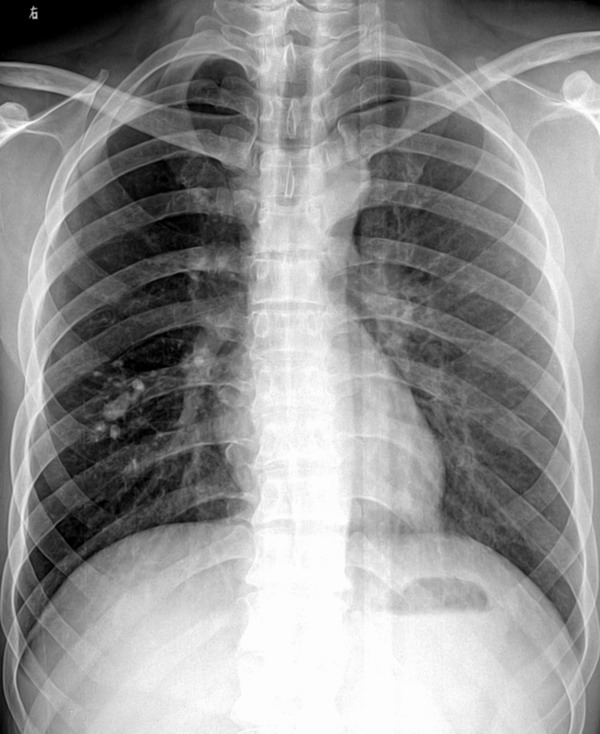

以下是引用jiangjing在2007-5-10 19:02:00的发言:[br]右下肺钙化,右肺透过度增强[密度减低]。考虑感染性病变所致

以下是引用小初学者在2007-5-10 19:14:00的发言:[br]考虑结核钙化可能性大